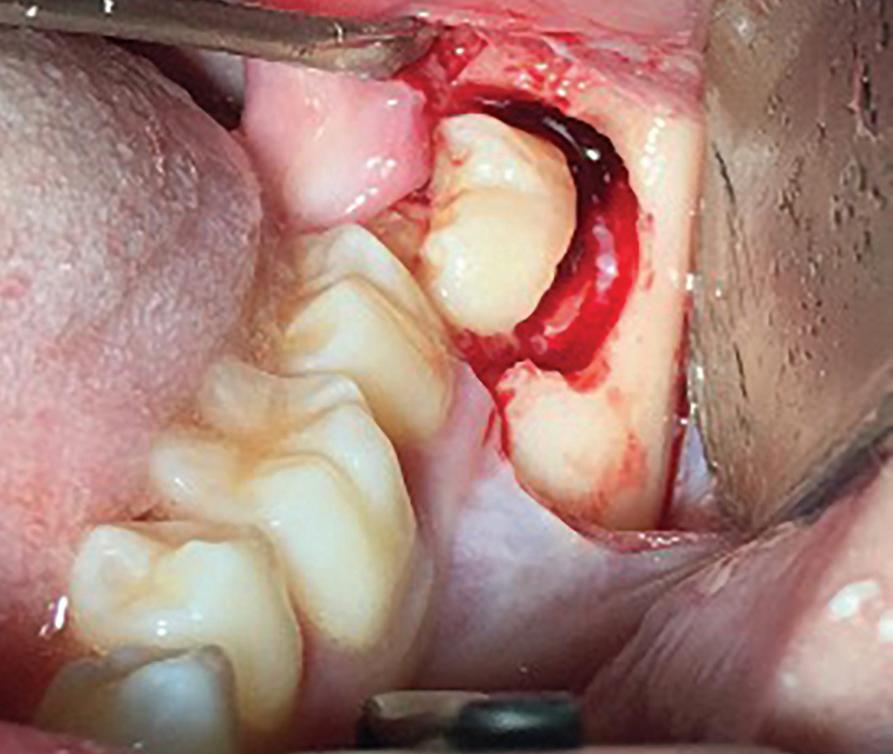

54 Oral and Maxillofacial Surgery

Root migration after coronectomy of impacted mandibular third molars: case reports

Gustavo Henrique de Souza Silva Enzo Balestrero

Jéssica Lemos Gulinelli

Pâmela Leticia dos Santos